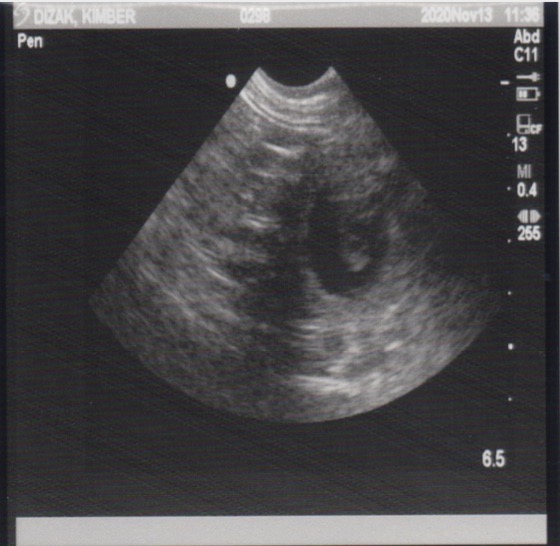

November 13, 2020 – Ultrasound

Since this was an artificial insemination and the success rate a bit lower than natural breedings, we wanted to have an ultrasound done to see if there are any little beings growing inside of Miss Kimber. Well, our repro vet confirmed this morning that Kimber is indeed pregnant!